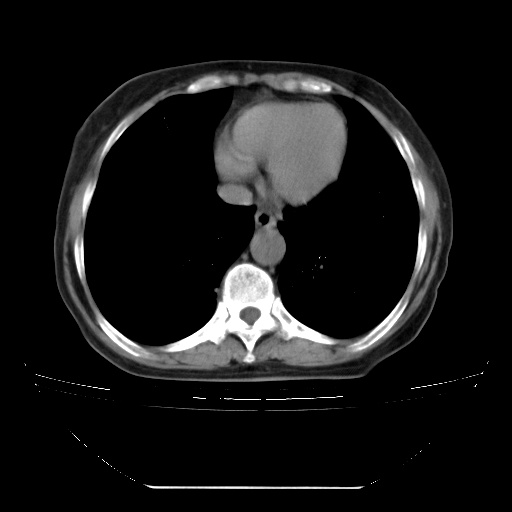

患者女性,72岁,慢性咳嗽3月余,曾抗炎治疗无效果,最近抗结核治疗约半月余,症状缓解。

ct示两肺粟粒状病灶,以两肺上叶尖后段及下叶背段分布为主;首先考虑结核。请战友们分析。

两肺内病灶呈小结节状和树芽状,纵膈的肿大的淋巴结密度不均匀,并见有钙化,考虑为两肺结核可能更大些。

两肺内病灶呈小结节状和树芽状,纵膈的肿大的淋巴结密度不均匀,并见有钙化,多形态病灶,考虑为两肺结核,肝内考虑小囊肿。

片子很好,质量很高,两侧肺门淋巴结肿大并有钙化,两肺弥漫病灶,首先考虑tb并播散,但年龄大了呀(72岁)小细胞肺癌不能除外,如果是肺癌也没什么大的治疗了,建议正规抗结核治疗后复查